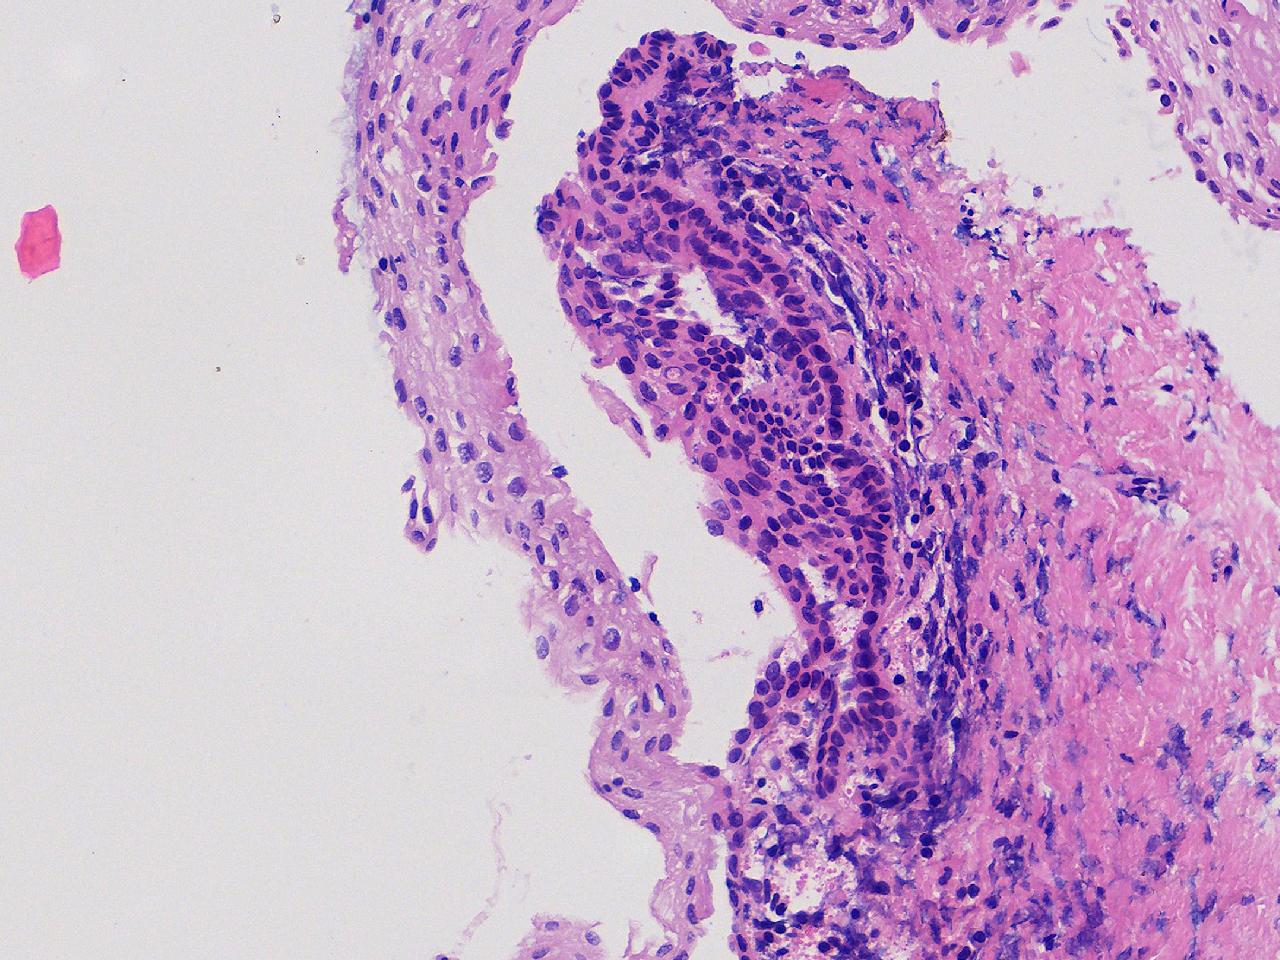

萎缩性? CIN1级?

女,64岁,宫颈活检,HPV不详。

宫颈活检

慢性宫颈炎

萎缩